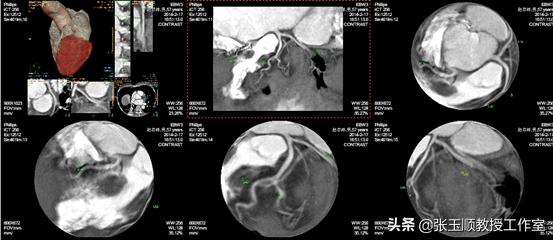

支气管镜检查:双侧支气管粘膜炎症改变、右下叶后段支气管粘膜炎性改变;24小时动态心电图未见心律失常,256层冠脉和肺血管CT均未见异常。心脏超声和腹部器官超声检查亦未见异常。不幸的是医院仍难以找不到解释王先生病情的原因。

图3冠脉和肺血管CTA

心血管内科:患者心电图正常,冠脉CTA未见明显异常,肺动脉CTA未见肺栓塞及肺动脉瘘或肺动静脉异位分流,排除了冠状动脉粥样硬化性心脏病及肺动-静脉瘘。